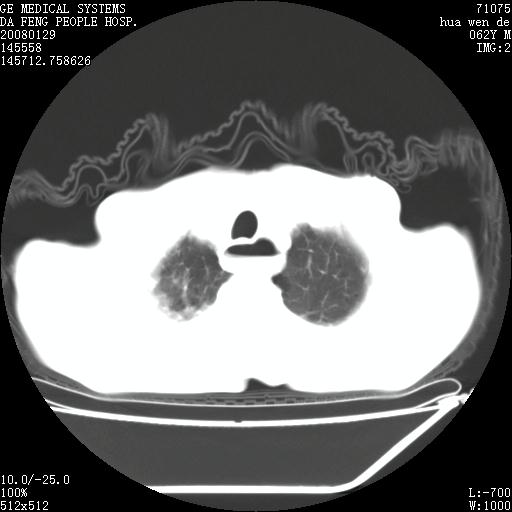

男性,67岁。作肺部检查时发现

右肺脓肿 胸腔胃

考虑1、右肺周围型肺癌可能性大。

2、贲门失迟缓症可能,建议钡餐检查。

考虑:胸腔胃并支气管瘘(并发肺炎,肺脓肿形成)。

理由:1、右上肺内病灶,空洞形成,有液平。

2、肺内多处炎症。

3、前段肺内炎症,支气管引流通畅,与肿块无关系。

1.整个食管扩张,未见明显占位性病变,贲门区亦未见明显占位病变,考虑:贲门失驰缓症;

2.右上肺病变边缘可见毛刺,囊壁厚度不均匀,周围境界较清楚,未见炎性渗出性影,右上肺外带可见片状影,边缘不清,考虑:肺癌伴空洞形成、右上肺炎。

食管全程扩张,壁均匀不厚,喷门失弛缓症

右上肺空洞可见液平,临近肺野磨玻璃密度,考虑1.结核2.脓肿